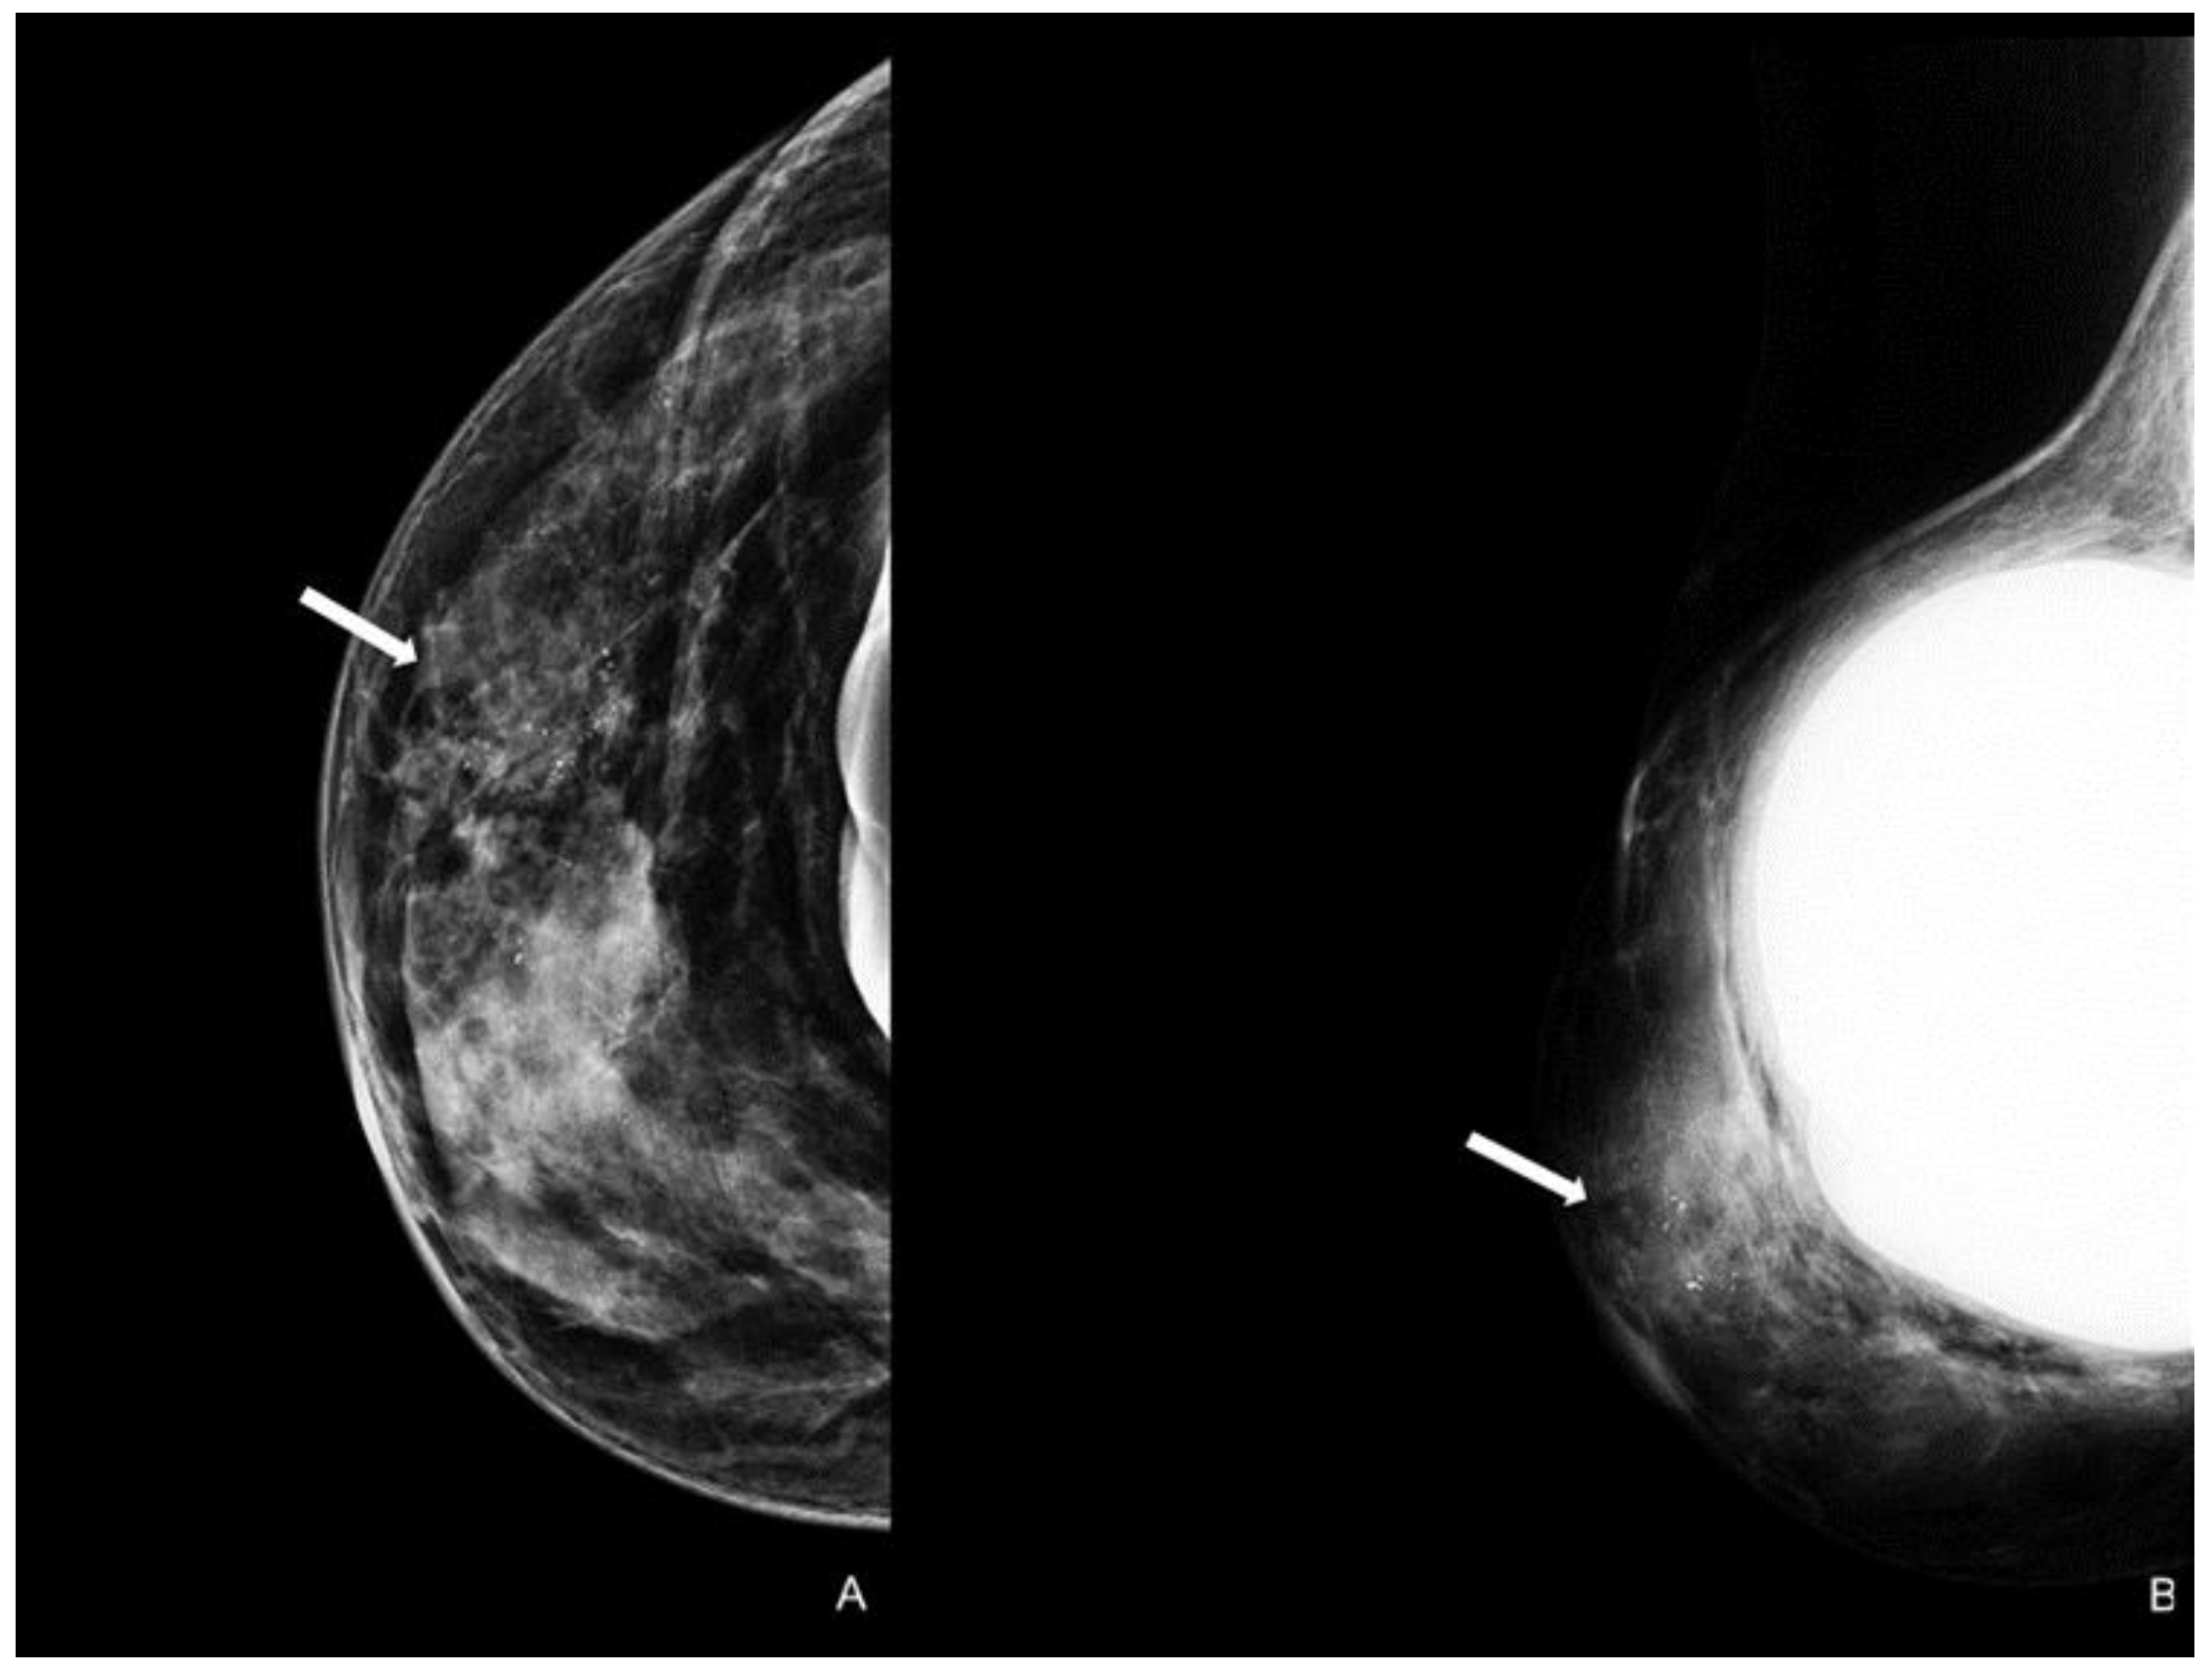

Figure 4.

Woman with a bilateral breast augmentation and a history of recurrent eczema of the right nipple. A skin biopsy was performed, and MPD was confirmed. Unilateral craniocaudal (A) and oblique (B) mammograms of the right breast show periareolar skin thickening and diffuse fine pleomorphic microcalcifications (arrow). The patient underwent a stereotactic biopsy and was diagnosed with high-grade in situ ductal carcinoma.

A careful and timely evaluation, including clinical examination with imaging techniques integration (as DM, US, and MRI), is always required in all patients with NAC skin changes to exclude MPD. However, a conclusive diagnosis invariably necessitates histological scrutiny. In addition to the typical clinical skin features, a thorough clinical breast examination is essential for detecting potential masses and axillary lymphadenopathy, which are indicators of underlying infiltrative pathology [45]. Specific imaging patterns have also been documented. A thorough mammographic assessment needs a digital system with an integrated tomosynthesis technique and magnification views of the NAC and the breast anterior third for detecting any underlying lesions and ruling out multifocal disease, as MPD has reported prevalence rates of 41% and 34% for multifocality and multicentricity, respectively [46]. Notable DM findings include thickening cutaneous or nipple and periareolar skin retraction [15]. Malignant microcalcifications along with a subareolar mass may be present, limited to the retroareolar region or elsewhere in the breast (Figure 4). However, DM sensitivity and specificity are limited: abnormal mammographic findings involving the NAC are not specific for MPD, especially in women with prior surgery or RT; in addition, DM may appear negative in 22–25% of patients, leading to a potential underestimation of disease extent [41,47].